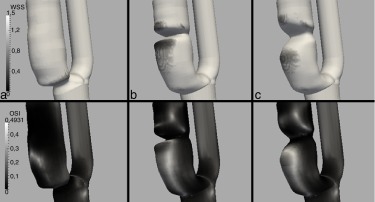

En la figura 7 se muestra el por debajo de 1,5 Pa y el OSI, con el objeto de analizar valores bajos y oscilantes simultáneamente de WSS que puedan ocasionar un riesgo de crecimiento de la placa por HI. Se observa que solo se registran en la parte distal de la estenosis en los modelos B y C. En ambos casos, el riesgo es bajo (no se sitúan claramente por debajo de 0,5 Pa), aunque algo superior en el modelo B que en el C, pues es más oscilante.

Carótidas idealizadas. Arriba: WSS¯ en Pa mostrando solo los valores por debajo ...

Figura 7.

Carótidas idealizadas. Arriba: en Pa mostrando solo los valores por debajo de 1,5 Pa. Abajo: OSI.

En la figura 8 se muestra el WSS promediado en un ciclo cardíaco, el y el TE con un umbral de 30 Pa. Como se observa, en la zona cercana a la placa se registran valores de altos, de hasta 32 Pa, con un TE del 31% a tensiones de cizallamiento superiores a 30 Pa. Estos valores implican un riesgo alto de embolización [26]  and [6] . En cambio, no se dan valores de por debajo de 0,5 Pa, que es el umbral por debajo del cual hay riesgo de formación de placa [23] , lo cual implica que el riesgo de que la placa siga progresando es bajo.

Caso clínico. Izquierda: WSS medio en un ciclo cardíaco, WSS¯ en Pa. Derecha: TE ...

Figura 8.

Caso clínico. Izquierda: WSS medio en un ciclo cardíaco, en Pa. Derecha: TE correspondiente a un WSS superior a 30 Pa, en porcentaje del período.